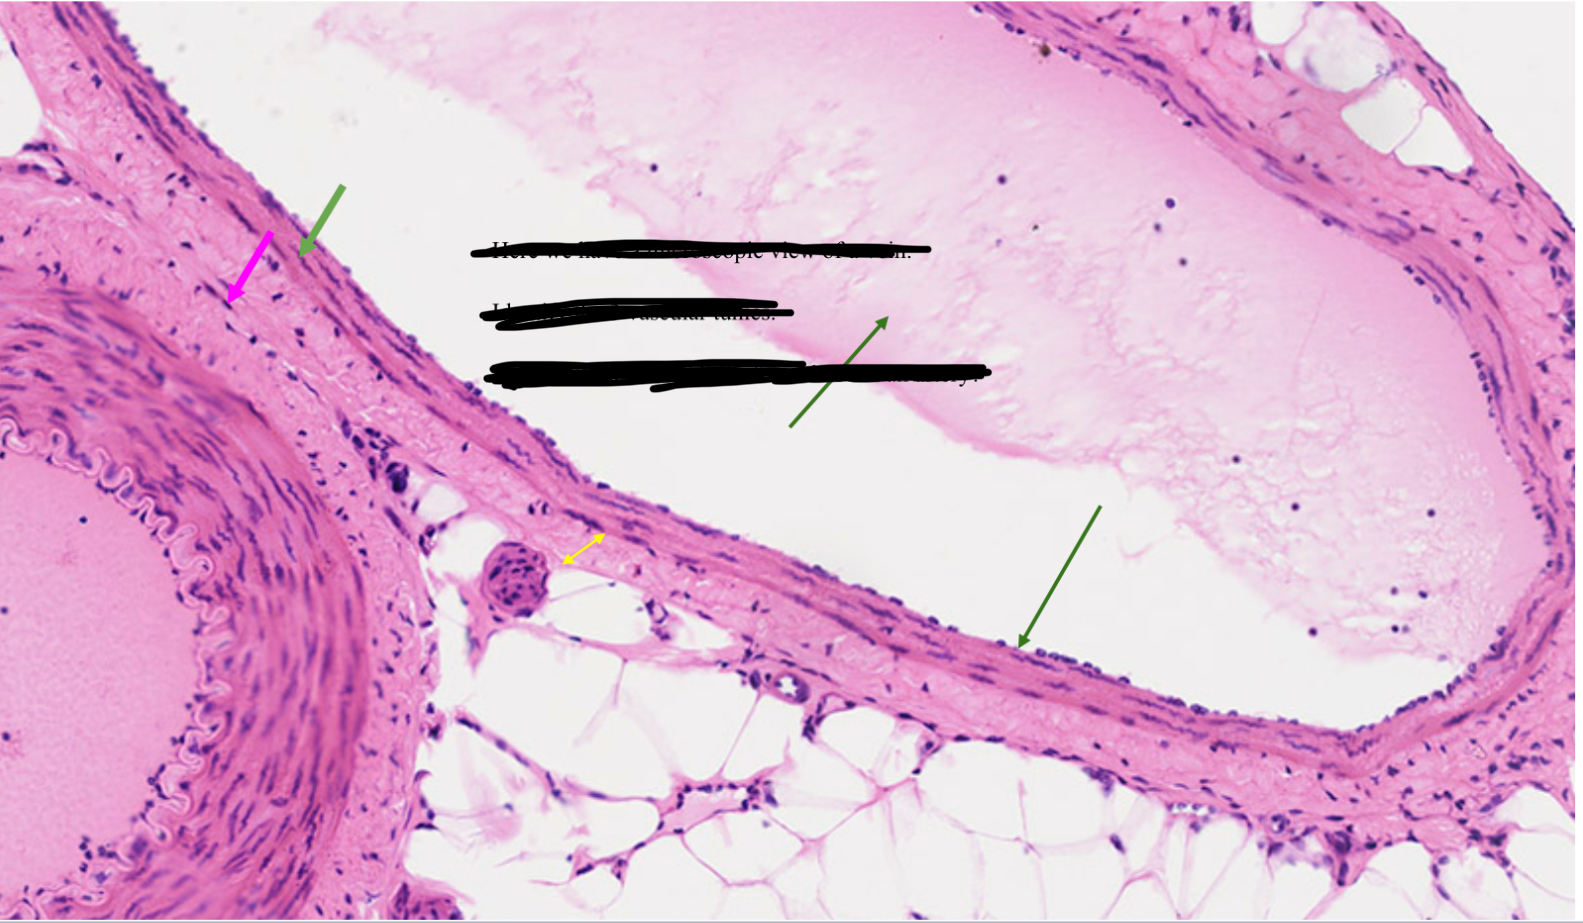

Vein

Artery or vein?

Tunica interna

Name the green

Tunica media

Name the pink

Tunica externa

Name the yellow